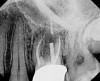

CBCT can be used to aid in further assessment of a previously endodontically treated tooth. A study by Uraba et al demonstrated that CBCT imaging is 20% more effective in detecting periapical lesions that cannot be detected on a periapical radiograph (Figure 1 and Figure 2).7 Diagnostic CBCT can provide additional information in comparison to periapical radiographs when treatment planning an endodontic retreatment case.8 The use of a limited field of view (FOV) CBCT on a patient that presents with a problem on an existing endodontically treated tooth can allow the clinician to critically evaluate the quality of the existing canal(s) obturation, identify any missed canals, and assess the extensiveness of a periapical lesion.

Periapical radiograph of tooth N o. 14 does not definitively reveal

a periapical radiolucency.

Fig 1.

CBCT of the same tooth N o. 14 (palatal

view exposure) shown in Fig 1 definitively shows a periapical lesion.

Fig 2.